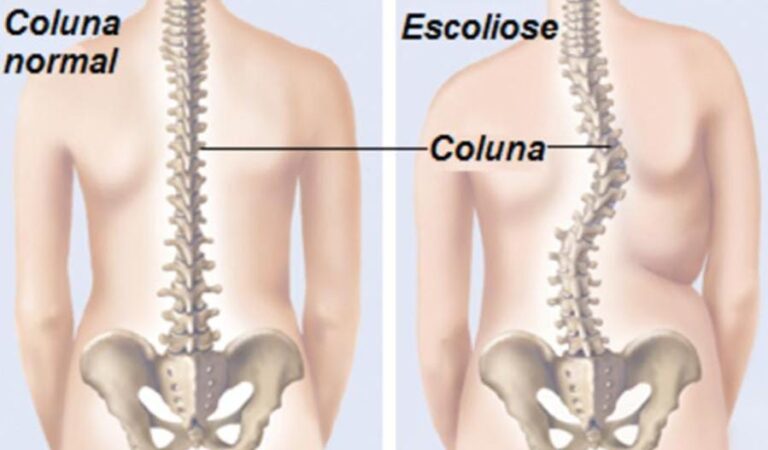

Tratamento de Escoliose com Método Escoliose Brasil

Como profissional formado pelo Curso Escoliose Brasil, aplico um tratamento personalizado e científico para escoliose, baseado em exercícios específicos e correção tridimensional (3D).

Cada paciente é avaliado detalhadamente, permitindo desenvolver um plano que corrige os desvios, melhora a postura e preserva a qualidade de vida.

Com acompanhamento constante, nosso objetivo é gerar resultados reais e duradouros, proporcionando movimento, conforto e uma vida mais independente.

A escoliose costuma aparecer por volta dos 10 aos 14 anos, principalmente em garotas.

Como é uma patologia progressiva, todo cuidado é necessário para estabilizar a curvatura.”